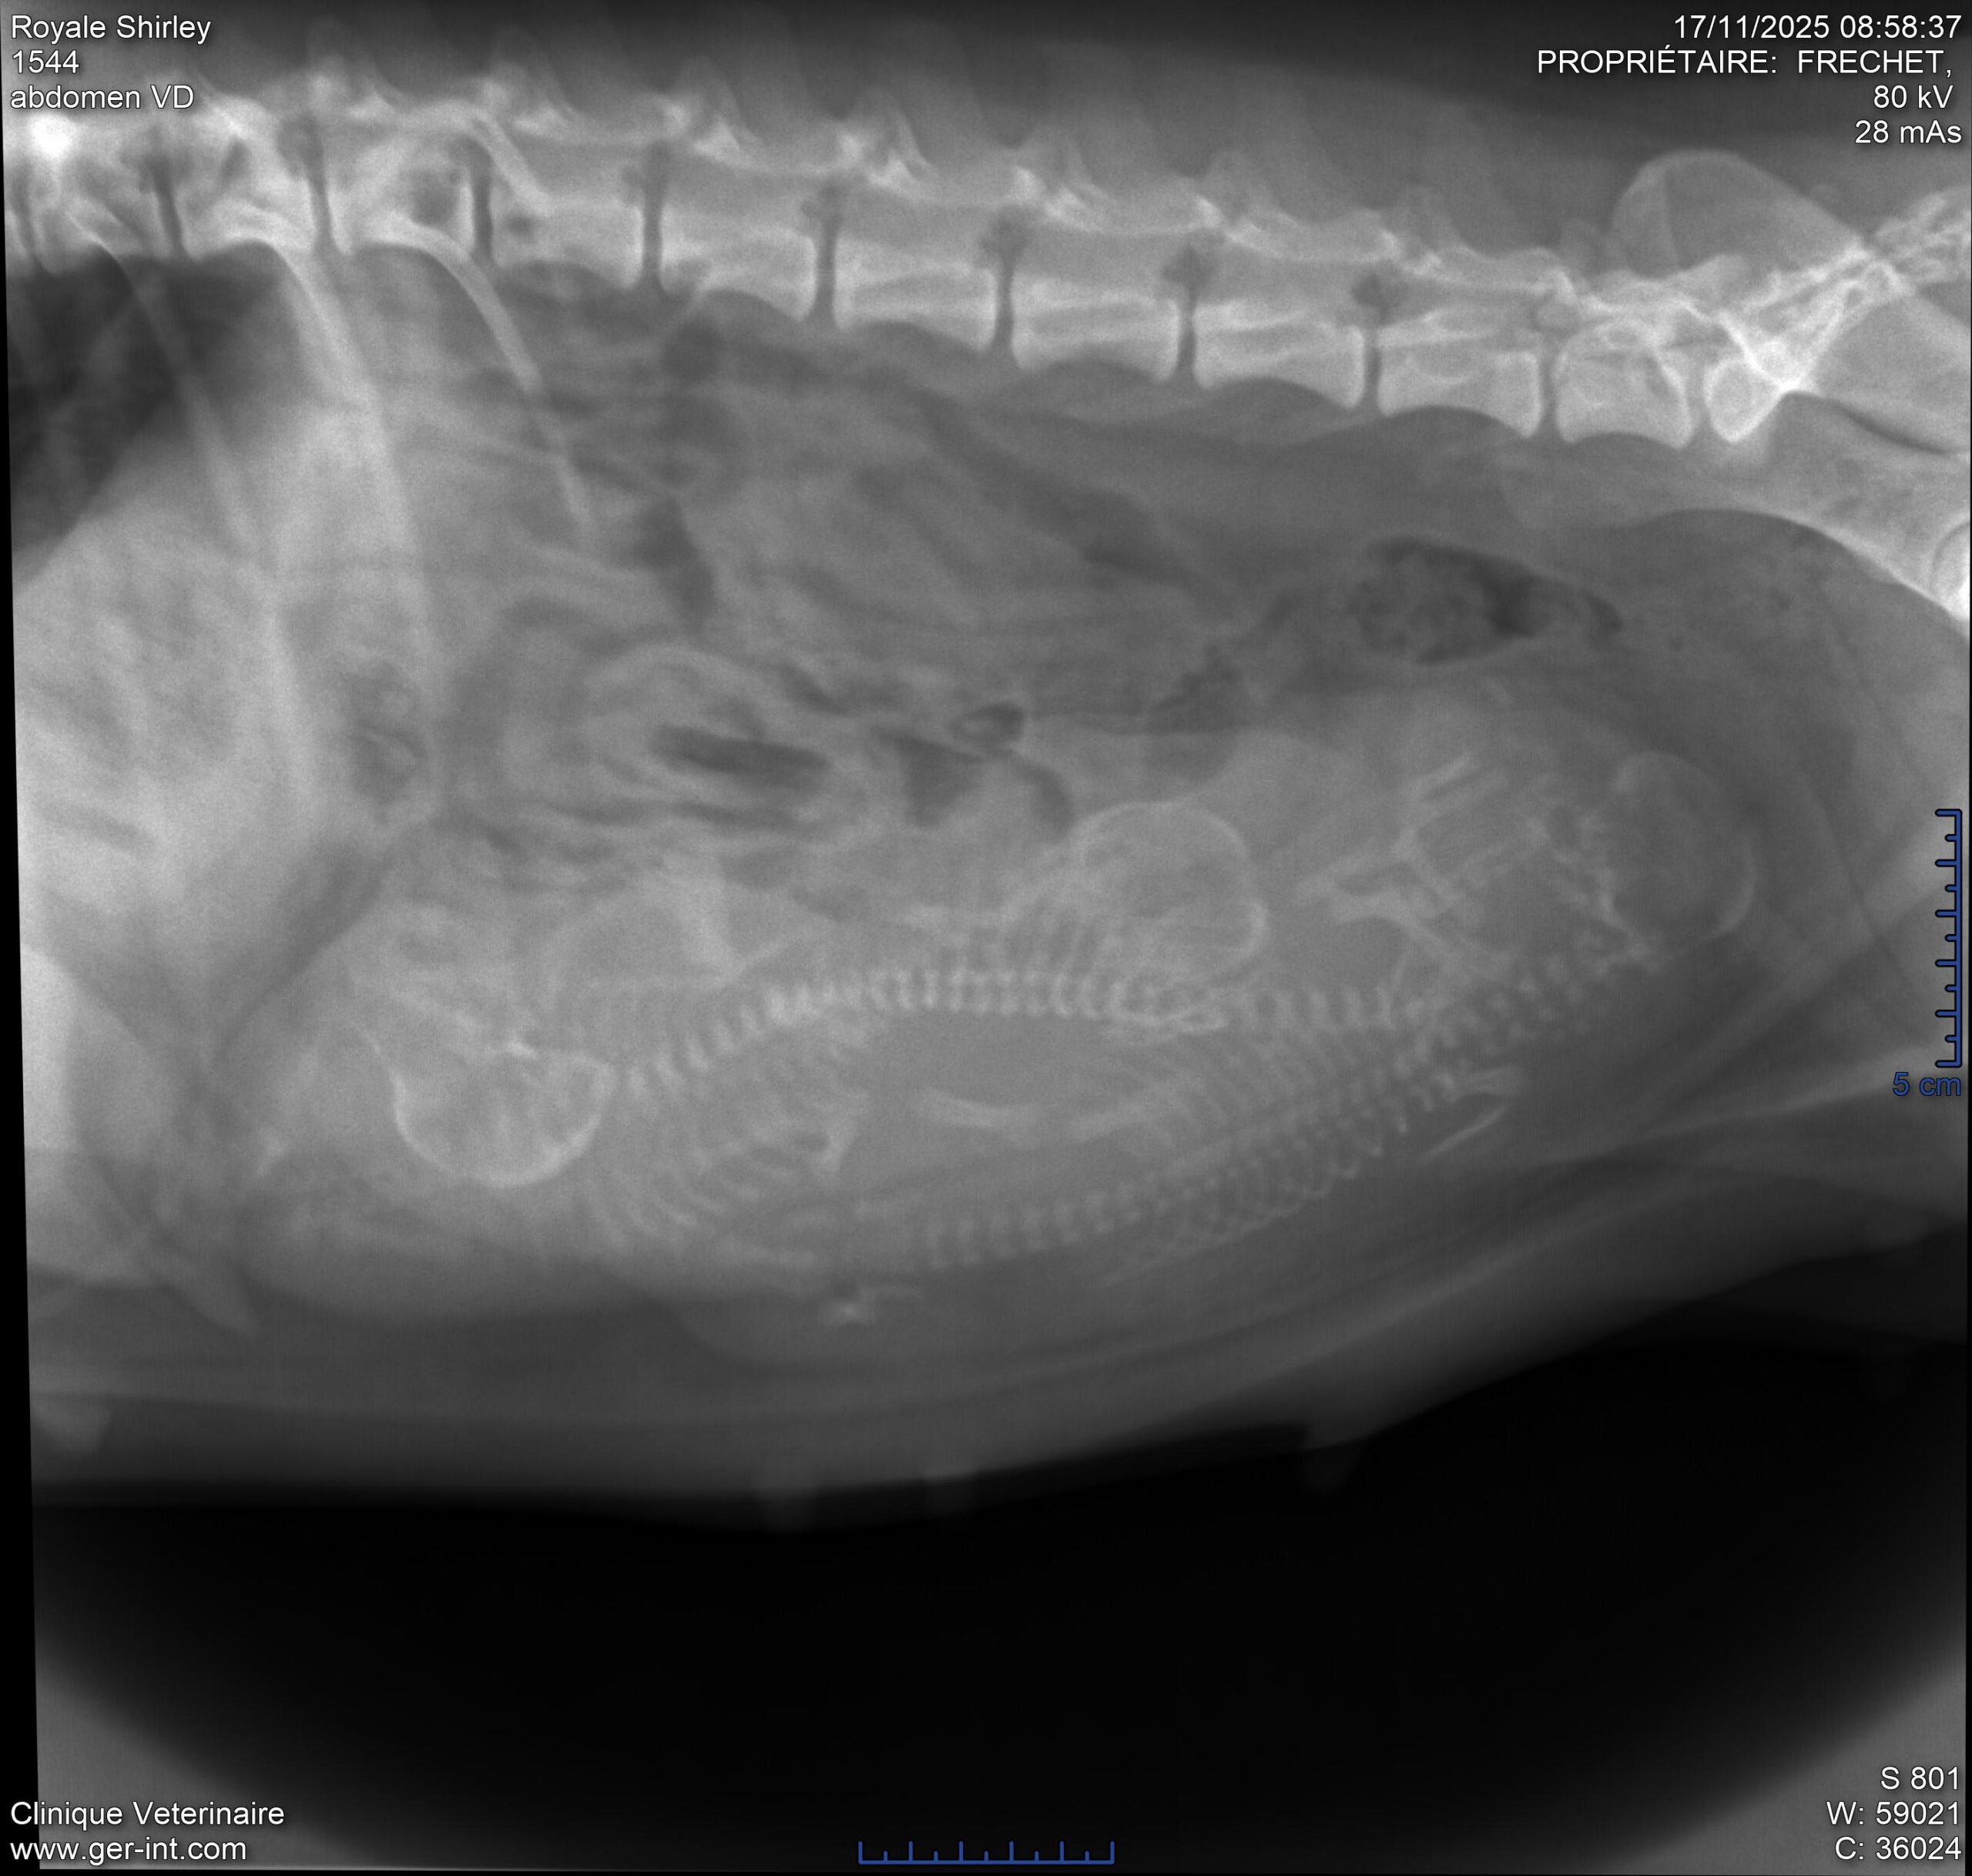

Dans chaque regard de Golden, il y a une leçon d’amour inconditionnel!